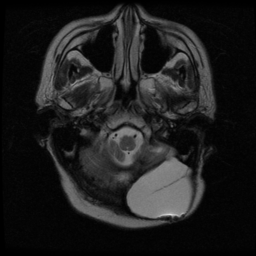

![]() |

| (a) | (b) | (c) | (d) |

Unsupervised Categorization: Our category discovery clusters are generally visually coherent within the cluster and size-balanced across clusters. However, image clusters formed only based on text information (of radiology reports) are highly unbalanced [49], with three clusters inhabiting the majority of images. Note that our method imposes no explicit constraint on the number of instances per cluster. Fig. 6 shows sample images and their top-10 associated key words from two randomly selected clusters (more results are provided in the supplementary material). The LDPO clusters are found to be clinically or semantically related to the corresponding key words, which describe presented anatomies, pathologies (e.g., adenopathy, mass), their associated attributes (e.g., bulky, frontal) and imaging protocols or properties.

The category discovery clusters employing our LDPO method are found to be more visually coherent and cluster-wise balanced in comparison to the results in [49] where clusters are formed only from text information ( radiology reports). Fig. 7 Left shows the image numbers for each cluster from the AlexNet-FC7-Topic setting. The numbers are uniformly distributed with a mean of 778 and standard deviation of 52. Fig. 7 Right illustrates the relation of clustering results derived from image cues or text reports [49]. Note that there is no instance-balance-per-cluster constraints in the LDPO clustering. The clusters in [49] are highly uneven: 3 clusters inhabit the majority of images. Fig. 6 shows sample images and top-10 associated key words from 5 randomly selected clusters (more results in the supplementary material). The LDPO clusters are found to be semantically or clinically related to the corresponding key words, containing the information of (likely appeared) anatomies, pathologies (e.g., adenopathy, mass), their attributes (e.g., bulky, frontal) and imaging protocols or properties.